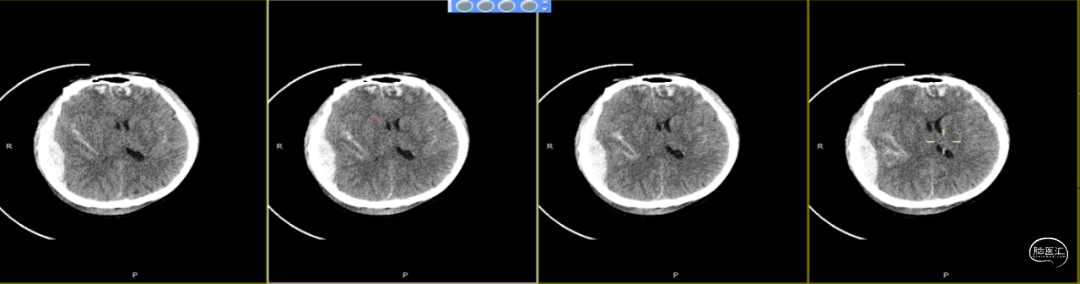

查体:嗜睡-昏睡状态,精神差,刺激睁眼,简单应答,肢体活动简单从嘱。GCS13分。双侧瞳孔等大等圆,直径2.5mm,对光反射灵敏,伸舌欠合作。转头、耸肩欠合作,四肢肌力4级,肌张力正常,颈抵抗(+),双Babinski sign未引出。枕部可见约5*4cm皮下血肿,压痛,拒按。周身多发片状皮肤擦伤。颅脑CT:双侧额叶脑挫裂伤;右侧顶颞枕部硬膜外、硬膜下血肿;蛛网膜下腔出血;右侧颞骨骨折累及右侧人字缝、顶乳缝,右侧顶乳缝旁小骨片;头皮软组织损伤、局部皮下血肿;双肺挫伤可能。

因患者在病情观察期间意识状态变差,昏睡-浅昏迷状态,予以急症手术治疗,清除硬膜外血肿,鉴于术中脑组织压力不高,予以骨瓣回置,术后严格控制血糖水平,常规使用抗生素(头孢唑林钠)预防感染。

术后第1天颅脑CT复查(如上图)